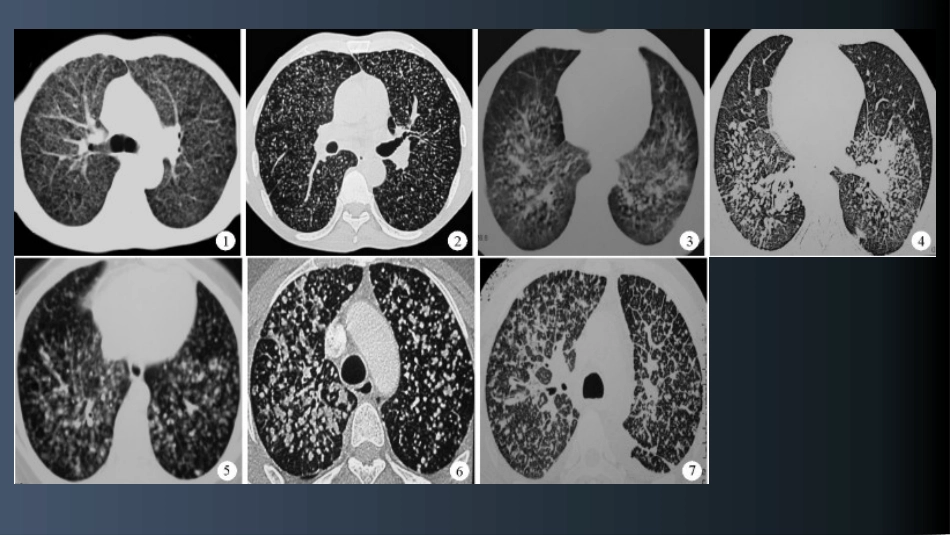

粟粒性肺结核、尘肺和粟粒性肺转移瘤的HRCT鉴别诊断褚志刚,余建群*,袁红梅,原珍团,张优仪.粟粒性肺结核、尘肺和粟粒性肺转移瘤的HRCT鉴别诊断.华西医学2009,24(6).2018.8.22摘要目的:探讨粟粒性肺结核、尘肺和粟粒性肺转移瘤的HRCT表现及鉴别特征方法:回顾性分析经本院临床证实的粟粒性肺结核38例,尘肺33例和粟粒性肺转移瘤41例的常规CT及HRCT资料,观察结节的大小、分布特点,统计分析三者的差异。结果:大小分布均匀清晰磨玻璃粟粒性肺结核313634全肺野32内中外均匀29全小叶33尘肺9317中上肺野30内中30小叶中心分布28粟粒性转移瘤41621中下肺野27外带34小叶实质36检查方法:西门子SENSATION4、16排CT机。均于深吸气末自肺尖至肺底行螺旋CT扫描。平扫扫描参数:电压120kV电流200mA螺距1.5cm重建层厚10mm。窗宽1800HU,窗位-400HU观察肺部病变。HRCT扫描参数:电压140kV电流200mA层厚1.5mm间隔3mm矩阵512×512,高分辨率重建算法。观察内容:①结节在肺野的分布(上、中、下肺野;肺内、中、外带)。按照第二、四肋骨前端下缘水平线为上、中、下野的分界,每侧肺纵行等分为内、中、外三带。②结节在肺小叶水平上的分布,包括小叶中心分布:结节位于小叶核邻近或包绕小叶核;小叶间隔分布:结节位于胸膜下和小叶间隔内;小叶实质分布:结节位于小叶中心与小叶间隔之间;全小叶分布:结节广泛分布于小叶各部位。③肺部合并征象毛玻璃征、肺气肿、增殖灶、钙化及空洞的有无等统计学方法:将三种疾病的HRCT表现数据输入SPSS10.0统计软件包后,分别对各种HRCT表现进行统计分析,采用卡方检验,比较率的差别。α取值为0.05,P<0.05为有统计学意义,计算出对于三者鉴别诊断具有统计学意义的HRCT表现。结果:粟粒性肺结核的结节双肺分布及大小均匀,边界多清晰,全小叶分布为主;肺内多合并增殖灶、磨玻璃征(ground-glassopacity,GGO)和肺气肿征;尘肺的结节以中上肺野和内中带分布为主,大小多不均匀,边界清晰,以小叶中心分布为主,常合并间隔旁或瘢痕旁肺气肿及钙化灶,磨玻璃征少见。粟粒性肺转移瘤的结节以中下肺野和中、外带分布为主,大小不等,边界多清晰,以小叶实质分布为主。讨论HRCT对肺部微细结构的显示优势及肺小叶解剖:HRCT是在薄层扫描的基础上进行骨窗算法重建的图像,可以清晰显示肺部的细微结构或微小病变。粟粒性肺结核、Ⅱ期尘肺和部分血行转移性肺肿瘤均可表现为肺部粟粒结节,三者常难以鉴别,但其治疗和预后均不同,因此需要认真判定。而且这些结节主要分布于间质结构内,常规CT不能很好显示三者结节在肺小叶水平分布的差别,而HRCT可全面地显示三种疾病结节分布的特点,有利于影像诊断及鉴别诊断。肺小叶由小叶间隔、小叶核心和小叶实质三个基本部分构成[3~5],小叶间隔是小叶的壁,主要由脏层胸膜向肺内延伸形成,厚度约0.1~0.15mm,正常情况下CT上不常见到。小叶中心部分称为小叶核心,由供应肺小叶的小动脉、细支气管以及它们周围的结缔组织鞘组成。小叶实质即小叶间隔与核心间的肺组织,由肺泡和毛细血管组成(图8)。粟粒性肺结核的病理基础及HRCT表现特征病理基础:粟粒性肺结核是结核患者肺内外结核灶或淋巴结干酪样坏死破入附近静脉,一次多量同时入血后经右心播散于双肺形成[6]。结核杆菌入肺后沉积于肺毛细血管或肺泡间质内,逐渐形成肉芽肿,肉眼观呈直径约1~3mm的黄白色结节[7],在肺小叶水平结节主要分布于肺泡壁和小叶间隔内。结核杆菌同时还可引起肺血管和淋巴管的通透性增加,导致肺泡炎。HRCT表现特征:在HRCT图像上,粟粒性肺结核结节主要表现为全肺野均匀分布,大小一致,边缘清楚的小结节,结节分布特征与此型结核的病理特点不无关系。由于肉芽肿形成的时间比较一致,因此形成了结核结节分布、大小均匀的特征,在胸部X线片上有时仅表现为模糊、增多的肺纹理,结节不能清楚的显示。本组89.4%的病例肺内出现磨玻璃征也为本病的另一影像特征。HRCT还能清楚地观察到结节沿支气管血管束分布,表现为支气管血管束增粗,呈串珠状,其与“树芽征”结节不同,前者边界清晰分布均匀,而后者边界不清呈斑片状分布。尘肺的病理基础及HRCT表现特征病理基础:尘肺大多是由长期吸入含二氧化硅的粉尘所致,粉尘颗粒入肺至淋巴管内被...